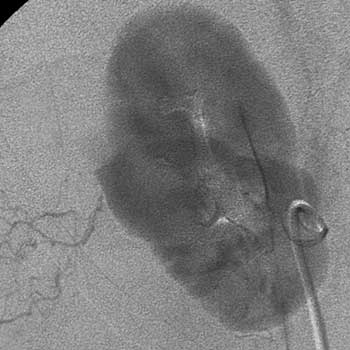

Рис. 9. Рак правой почки. Т1N0M0. В паренхиматозную фазу ангиографии определяется аваскулярное объёмное образование, нарушающее целостность контура почки.